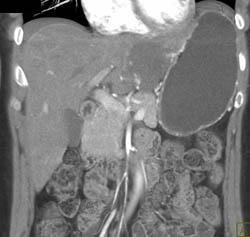

Partial Portal Vein Thrombosis With Esophageal and Gastric Varices